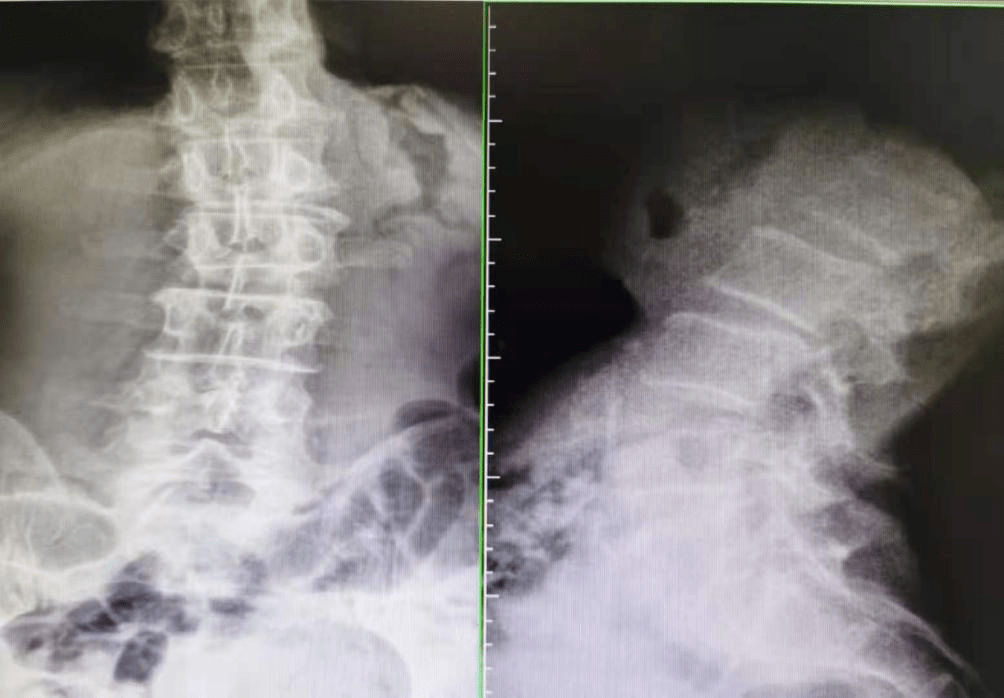

到了医院一检查 , 好嘛 , 这老腰 , 腰椎间盘突出、腰椎侧弯、腰椎滑脱、小关节紊乱 , 一个不落全有了!老李自己看到后都惊呆了 , “我就是擦个地 , 这腰咋就坏了?”